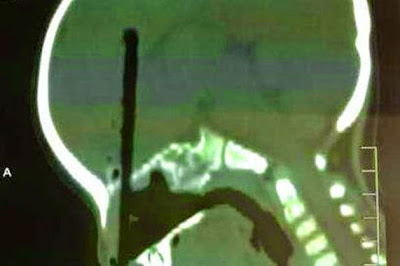

A 2 year old Chinese boy named Huang Zicheng had to have a chopstick removed from deep within his brain after he accidentally shoved it up his nose. The chopstick penetrated three inches into his brain and doctors who spent four hours carefully taking it out of the little boy's skull said if it had gone any further, it would have caused brain injury.

Thankfully, the chopstick did not damage any major nerves and arteries and Huang expected to make a full recovery. Continue...